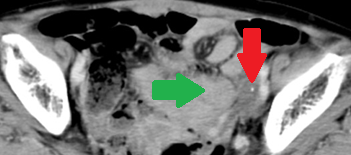

Abdominal CT scan after 2 years. Red arrow - Small residual neoplasm. Green arrow - Small bowel loops (Courtesy Dr. V. Penopoulos)